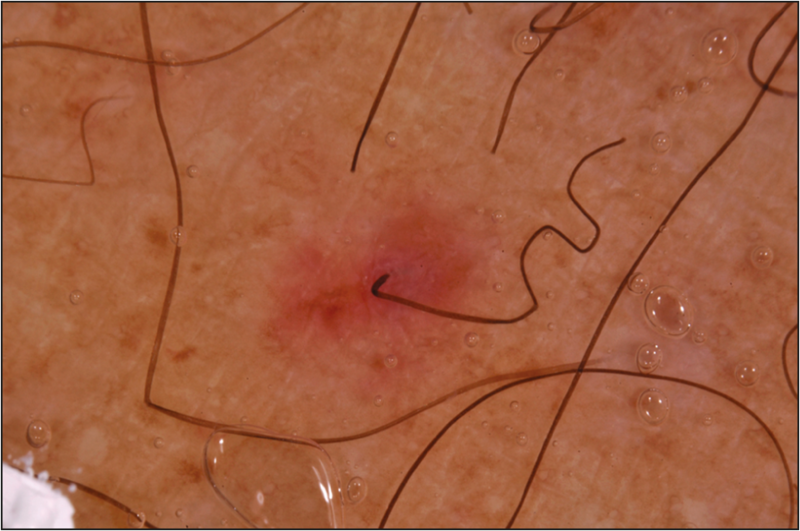

Corkscrew Hair A New Dermoscopic Sign for Diagnosis of Tinea Capitis What Are Corkscrew Hairs Zigzag hairs can be observed in tinea capitis and alopecia areata. corkscrew hairs are the hallmark of tinea capitis. trichoscopy is a useful method in the diagnosis of tinea capitis. the dermatoscopic findings are characteristic of tinea capitis and are thought to be the result of the invasion of. corkscrew hairs appear similar to a corkscrew. What Are Corkscrew Hairs.

Comma, Hook, Coiled and Corkscrew Hairs by Trichoscopy What do they What Are Corkscrew Hairs They are very coiled like a spring. corkscrew hairs appear similar to a corkscrew wine bottle opener. corkscrew hairs are the hallmark of tinea capitis. scurvy (scorbutus) is the clinical disease caused by vitamin c (ascorbic acid) deficiency with characteristic mucocutaneous and. the most characteristic (with a high predictive value) trichoscopic findings of tinea capitis included. What Are Corkscrew Hairs.